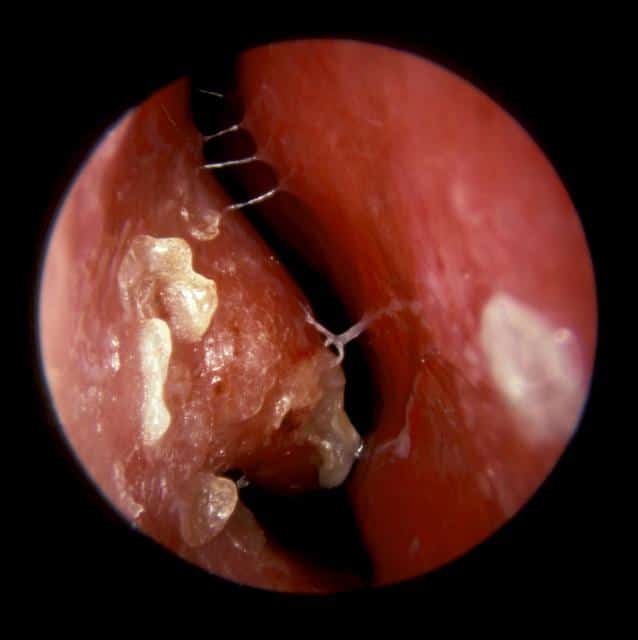

При осмотре носа можно заметить сероватые корочки. Также возможно развитие дерматита. Слизистая оболочка носа сильно воспалена и гиперемирована, часто имеет синеватый оттенок.

- эндоскопическое обследование носовой полости;